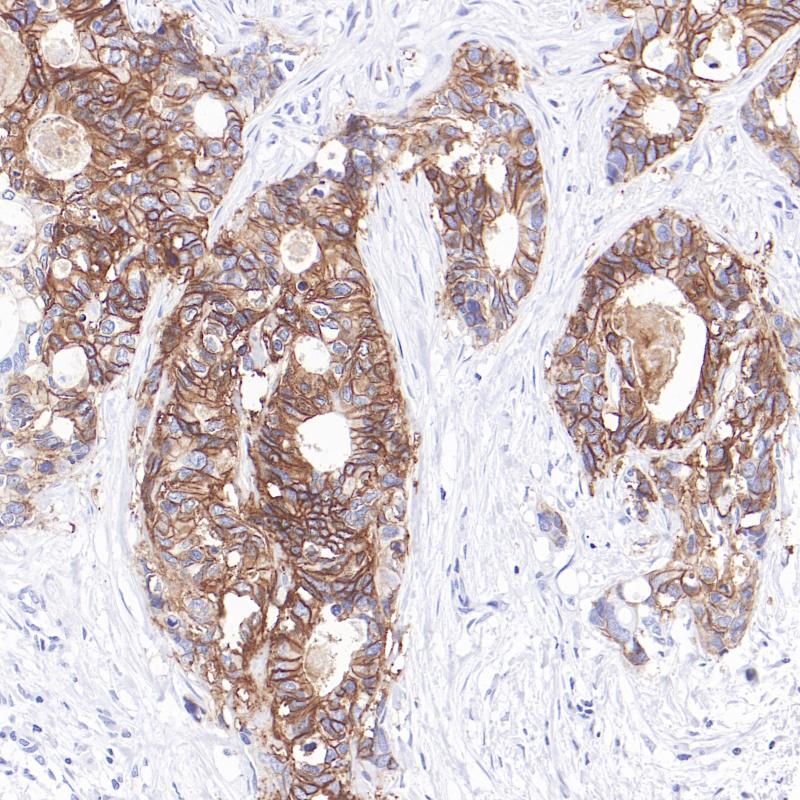

GPA33是免疫球蛋白超家族的新成员。GPA33蛋白在细胞-细胞粘附中起作用,并与形成稳定的细胞群落网络有关。GPA33主要在正常胃肠道上皮和95%的结肠癌中表达。GPA33与结直肠癌和炎症性肠病有很强的相关性。临床上,GPA33免疫组化主要用于结直肠癌诊断、分型与鉴别,是结直肠来源肿瘤的高特异性标志物。

阳性对照

结肠癌

亚细胞定位